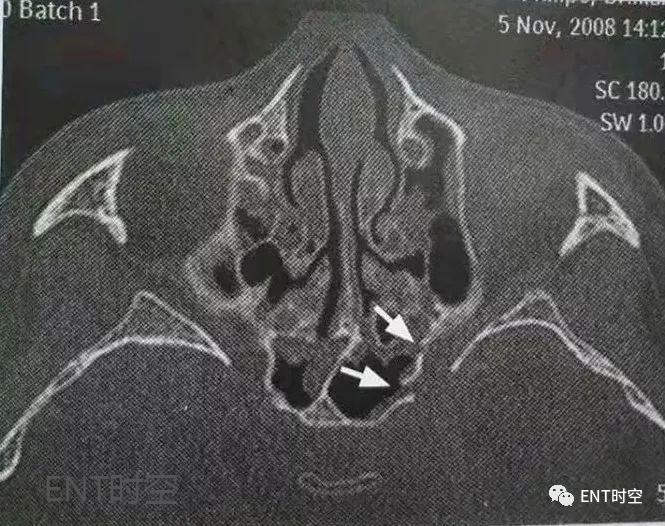

眼眶爆裂骨折(blow- out fracture)是眼眶骨折的一种常见类型,指*力暴**作用于眼球,将压力传入眶内,形成眶内壁、眶下壁向外突出的骨折,而眶缘没有骨折。目前,临床已开展眶壁整复手术治疗眼眶骨折,CT诊断眼眶骨折时应详细描述骨折的部位及累及的范围,同时还应描述眼外肌的改变及眶内脂肪突出的程度(图三)。

图3眶壁骨折,冠状位CT显示右眶内壁及眶下壁骨折移位;眶内容向筛窦疝出。箭头多示内直肌疝入筛窦。